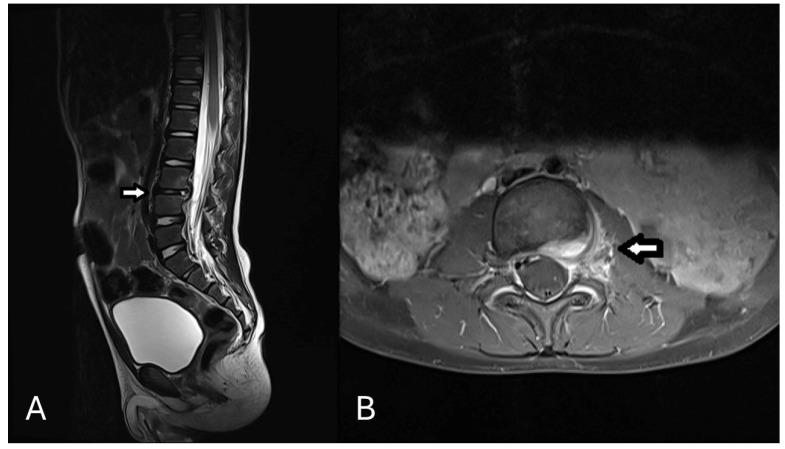

With an incidence of 0.3 per 100,000, spondylodiscitis is a rare condition in children. It is typically bacterial in origin and most commonly caused by . Bone involvement in cat-scratch disease (CSD) due to is exceedingly rare, occurring in only 0.17-0.27% of cases. We present the case of a 3-year-old boy with a two-week history of intermittent back pain and a recent onset fever. Initial laboratory findings were unremarkable, and MRI revealed spondylodiscitis at L3/4 without abscess formation. Empirical antibiotic treatment with ampicillin/sulbactam showed no clinical response. Serologic testing revealed a positive IgM (IgG negative), leading to a change in antibiotic treatment to azithromycin and rifampicin for three weeks, resulting in rapid clinical improvement. Follow-up at nine weeks showed marked clinical and radiologic improvement. Although IgM subsequently turned negative without IgG seroconversion-a pattern previously described in infections-this does not exclude the diagnosis. Biopsy or tissue PCR was not performed due to the mild clinical course. A review of the literature identified 28 pediatric cases of spondylodiscitis, with significant variation in diagnostic and treatment approaches. This case underscores the importance of considering in the differential diagnosis of pediatric vertebral osteomyelitis.

脊椎椎间盘炎在儿童中发病率为每10万人0.3例,是一种罕见疾病。其通常起源于细菌,最常见的病因是 。由 引起的猫抓病(CSD)累及骨骼极为罕见,仅在0.17 - 0.27%的病例中出现。我们报告一例3岁男孩病例,其有两周间歇性背痛病史且近期发热。初始实验室检查结果无异常,MRI显示L3/4椎体椎间盘炎,无脓肿形成。氨苄西林/舒巴坦经验性抗生素治疗无临床反应。血清学检测显示 IgM阳性(IgG阴性),抗生素治疗改为阿奇霉素和利福平,持续三周,临床症状迅速改善。九周后随访显示临床和影像学有显著改善。尽管IgM随后转为阴性且未出现IgG血清学转换——这是先前在 感染中描述过的模式——但这并不排除诊断。由于临床病程较轻,未进行活检或组织PCR检测。文献回顾发现28例儿童 椎体椎间盘炎病例,诊断和治疗方法差异很大。该病例强调了在儿童椎体骨髓炎鉴别诊断中考虑 的重要性。